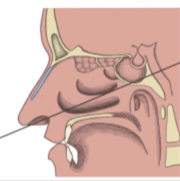

VII. CIRUGIA DE HIPOFISIS

Se complementerá y trabajará en conjunto con la clinica de hipofisis de endoncrinologia haciendo una discusion de los casos apoyandose en los consultores

con los que cuenta el grupo. Tomando la mejor decisión y mas adecuada conducta para cada paciente. Cirugia endoscopica transnasal y transcraneana microscópica

para patologia de hipofisis (NO Pos se debe crear tarifa institucional).